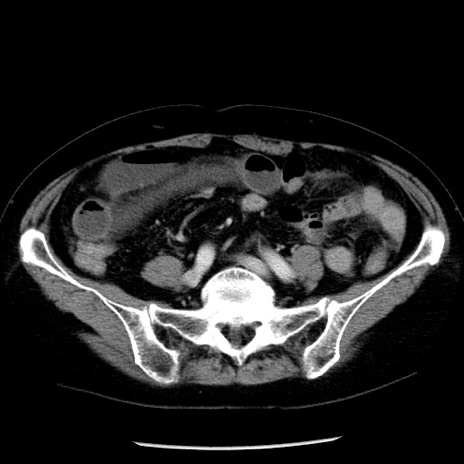

症例13(横断像)

【症例】70歳代女性

【主訴】腹痛、嘔吐

【現病歴】15時間程前(昨晩)より腹痛あり。今朝になっても症状の改善なく、嘔吐あり。腹痛も増悪あり、救急外来受診。

【既往歴】子宮癌全摘術後

【身体所見】意識清明、BP 121/72mmHg、P 74bpm、SpO2 100%(RA)、腹部:平坦・軟、腸雑音ほぼ聴取せず。下腹部・心窩部・臍左上に圧痛あり。反跳痛なし。

【データ】WBC 10600、CRP 0.15